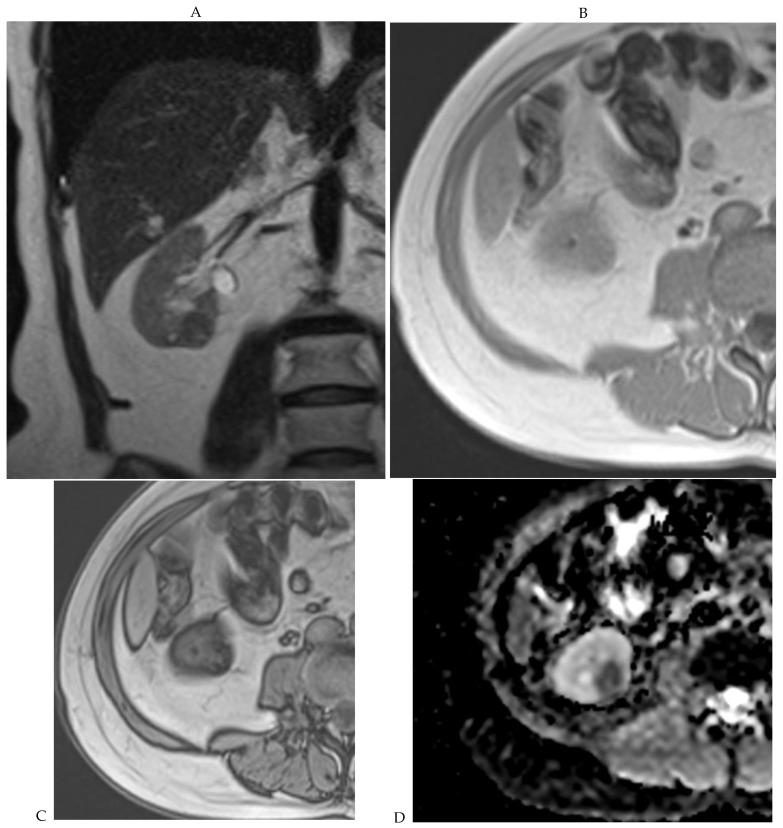

This review highlights recent advances in renal cell carcinoma (RCC) imaging. It begins with dual-energy computed tomography (DECT), which has demonstrated a high diagnostic accuracy in the evaluation of renal masses. Several studies have suggested the potential benefits of iodine quantification, particularly for distinguishing low-attenuation, true enhancing solid masses from hyperdense cysts. By determining whether or not a renal mass is present, DECT could avoid the need for additional imaging studies, thereby reducing healthcare costs. DECT can also provide virtual unenhanced images, helping to reduce radiation exposure. The review then provides an update focusing on the advantages of multiparametric magnetic resonance (MR) imaging performance in the histological subtyping of RCC and in the differentiation of benign from malignant renal masses. A proposed standardized stepwise reading of images helps to identify clear cell RCC and papillary RCC with a high accuracy. Contrast-enhanced ultrasound may represent a promising diagnostic tool for the characterization of solid and cystic renal masses. Several combined pharmaceutical imaging strategies using both sestamibi and PSMA offer new opportunities in the diagnosis and staging of RCC, but their role in risk stratification needs to be evaluated. Although radiomics and tumor texture analysis are hampered by poor reproducibility and need standardization, they show promise in identifying new biomarkers for predicting tumor histology, clinical outcomes, overall survival, and the response to therapy. They have a wide range of potential applications but are still in the research phase. Artificial intelligence (AI) has shown encouraging results in tumor classification, grade, and prognosis. It is expected to play an important role in assessing the treatment response and advancing personalized medicine. The review then focuses on recently updated algorithms and guidelines. The Bosniak classification version 2019 incorporates MRI, precisely defines previously vague imaging terms, and allows a greater proportion of masses to be placed in lower-risk classes. Recent studies have reported an improved specificity of the higher-risk categories and better inter-reader agreement. The clear cell likelihood score, which adds standardization to the characterization of solid renal masses on MRI, has been validated in recent studies with high interobserver agreement. Finally, the review discusses the key imaging implications of the 2017 AUA guidelines for renal masses and localized renal cancer.

本综述重点介绍了肾细胞癌(RCC)成像的最新进展。首先是双能计算机断层扫描(DECT),它在评估肾肿块方面已显示出较高的诊断准确性。多项研究表明碘定量具有潜在益处,特别是在区分低衰减、真正强化的实性肿块与高密度囊肿方面。通过确定是否存在肾肿块,DECT可以避免进行额外的影像学检查,从而降低医疗成本。DECT还可以提供虚拟平扫图像,有助于减少辐射暴露。该综述接着介绍了最新进展,重点是多参数磁共振(MR)成像在RCC组织学亚型分类以及肾良性与恶性肿块鉴别方面的优势。一种提议的标准化图像逐步解读方法有助于高精度地识别透明细胞RCC和乳头状RCC。对比增强超声可能是一种用于实性和囊性肾肿块特征化的有前景的诊断工具。几种同时使用锝[99mTc]甲氧基异丁基异腈(sestamibi)和前列腺特异性膜抗原(PSMA)的联合药物成像策略为RCC的诊断和分期提供了新机会,但其在风险分层中的作用有待评估。尽管放射组学和肿瘤纹理分析因可重复性差且需要标准化而受到阻碍,但它们在识别预测肿瘤组织学、临床结果、总生存期和治疗反应的新生物标志物方面显示出前景。它们有广泛的潜在应用,但仍处于研究阶段。人工智能(AI)在肿瘤分类、分级和预后方面已取得令人鼓舞的结果。预计其在评估治疗反应和推进个性化医疗方面将发挥重要作用。该综述接着重点介绍了最近更新的算法和指南。2019年版的博斯尼亚克分类纳入了MRI,精确定义了以前模糊的影像学术语,并允许将更大比例的肿块归类为低风险类别。最近的研究报告称,高风险类别的特异性有所提高,阅片者之间的一致性也更好。透明细胞可能性评分在MRI上对实性肾肿块的特征化增加了标准化,最近的研究已验证其具有较高的观察者间一致性。最后,该综述讨论了2017年美国泌尿协会(AUA)肾肿块和局限性肾癌指南的关键影像学意义。